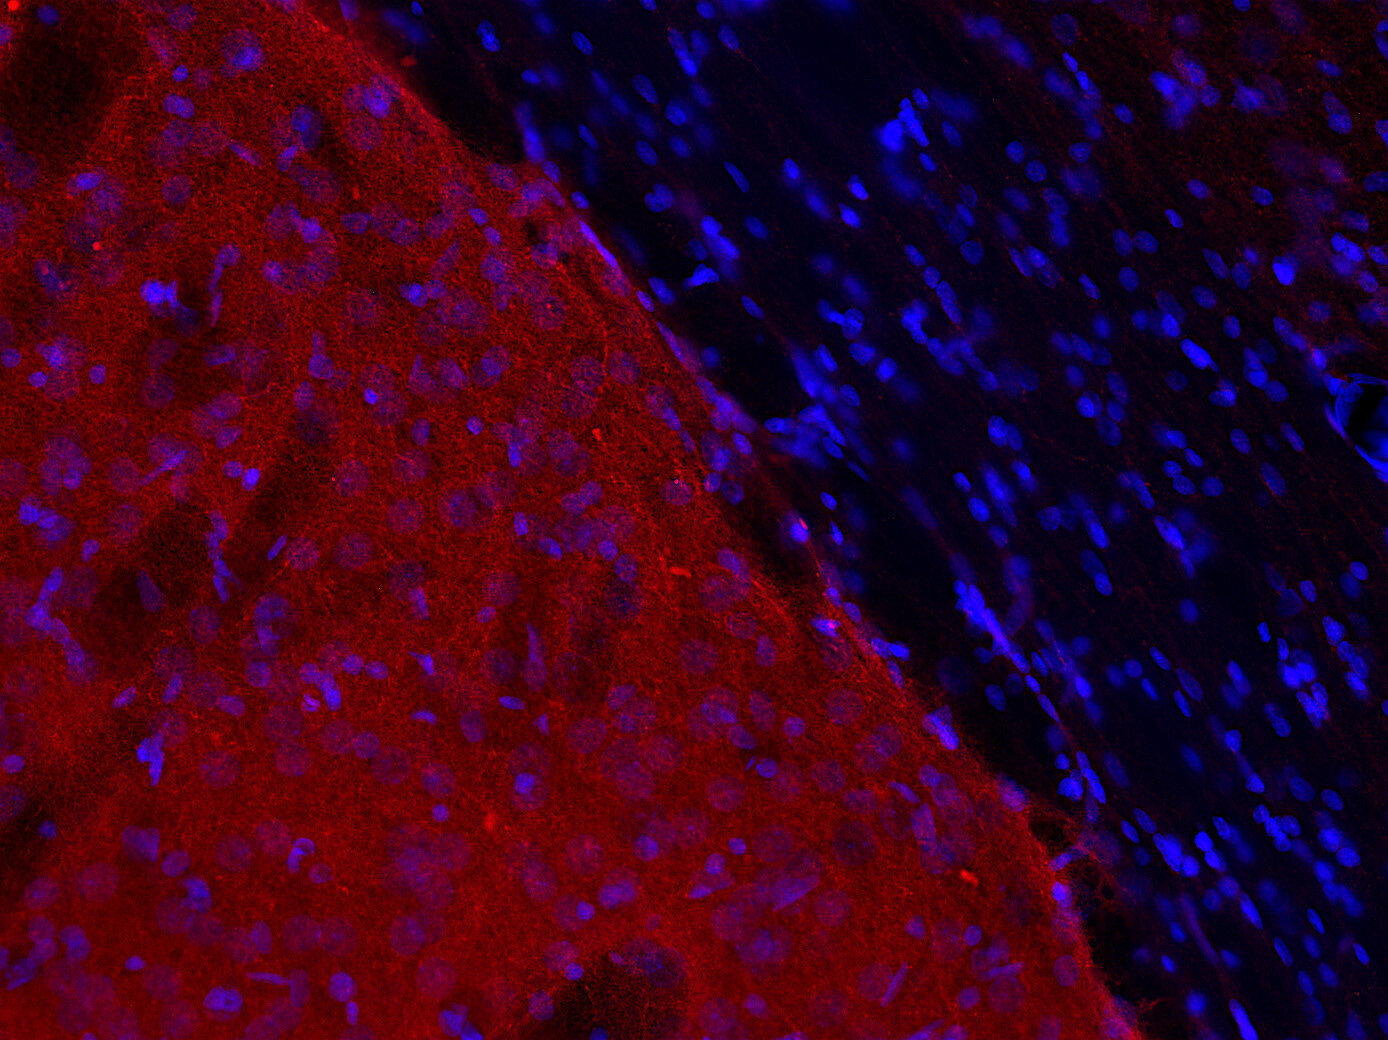

DOPA decarboxylase antibody - 369 004

IHC: 1 : 500 gallery

Immunohistochemistry (IHC) on 4% PFA perfusion fixed tissue with 24h PFA post fixation. Immunoreactivity is usually revealed by fluorescence or a chromogenic substrate. Some antibodies require special fixation methods or antigen retrieval steps. For details, please refer to the ”Remarks” section.

Specificity DOPA decarboxylase

DOPA decarboxylase, also referred to as aromatic L-amino acid decarboxylase, AADC or DDC, is the second enzyme in the biosynthesis of dopamine and serotonin. In addition, it is responsible for the synthesis of the trace amines phenylethylamine, p-tyramine, and tryptamine, which are considered to act as neuromodulators.

DDC is expressed in the central nervous system, but has also been detected in several tissues such as liver, kidney, small intestine, adrenal gland and blood vessels.